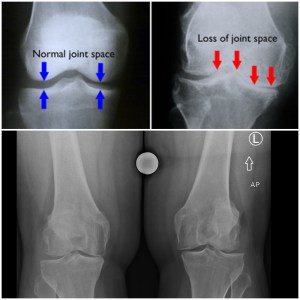

He took a look at the Xrays and diagnosed me with severe osteoarthritis. He said my knees were worse than a typical 60 year old’s knees. I would eventually need both knees replaced, but I was too young. So my orders were to stop running, keep losing weight, and use anti-inflammatories, as needed. And even if I did tear a meniscus, he couldn’t operate because I didn’t have enough cartilage left in my knee. If he cleaned up the meniscus, I would be even more bone on bone, and in worse shape.

The results from the MRI showed a torn meniscus, some bursitis and most debilitating, a severely misaligned patella.